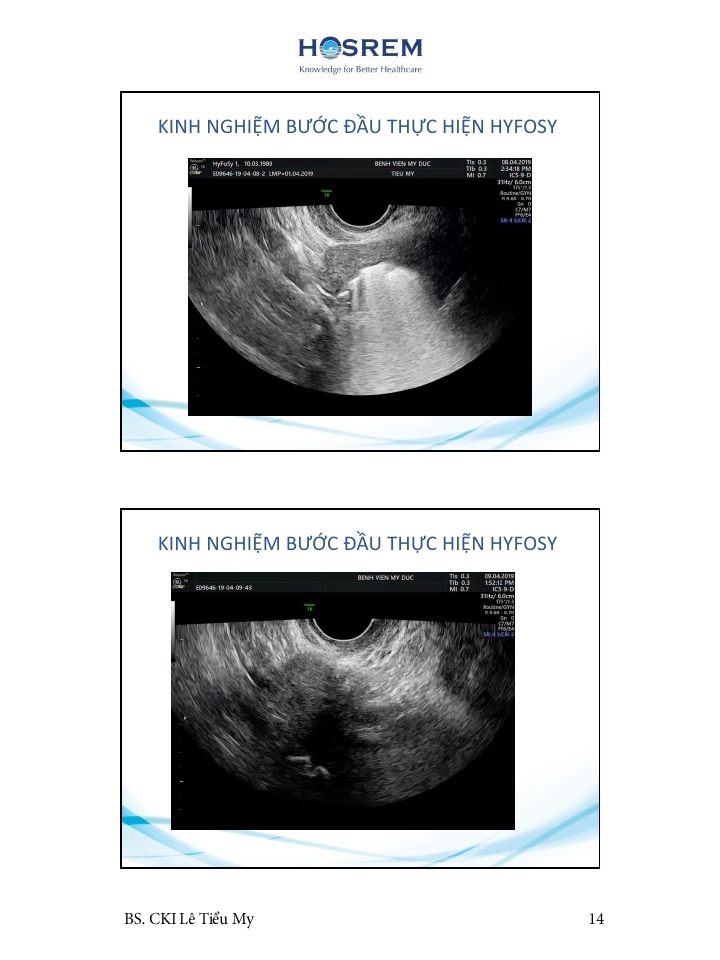

Các phương pháp đánh giá ống dẫn trứng